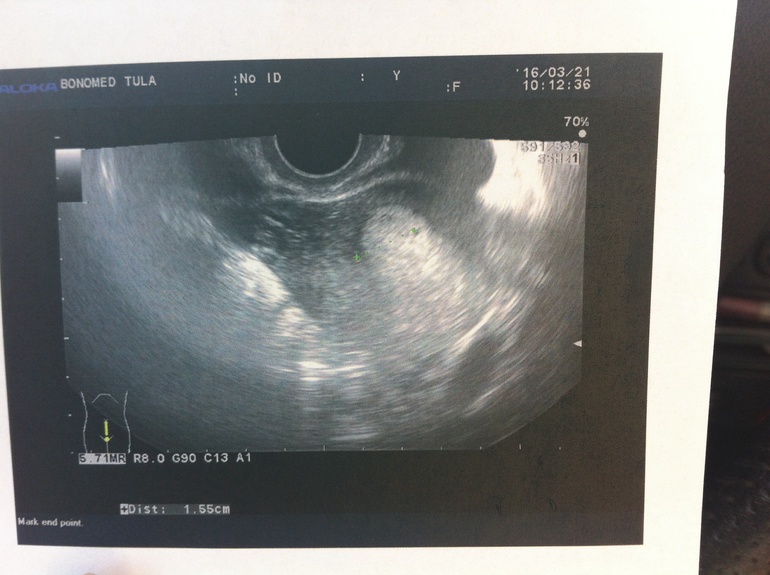

Узи 4 дня задержки

Узи 4 дня задержки 147 фото